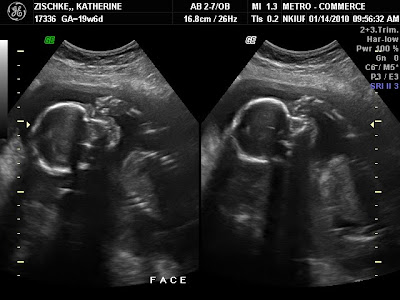

Ultrasound today confirmed that Baby #2 is a boy!  Here are a few pictures of the little guy.  Everything looked great and he was being very active for the camera.

There are two different pictures on each screen shot . . . there are NOT two babies!!

He had his hands up near his face most of the time.

The ultrasound tech got some neat pictures of his hands.  The baby was showing off a little and gave us the "thumbs up" sign.